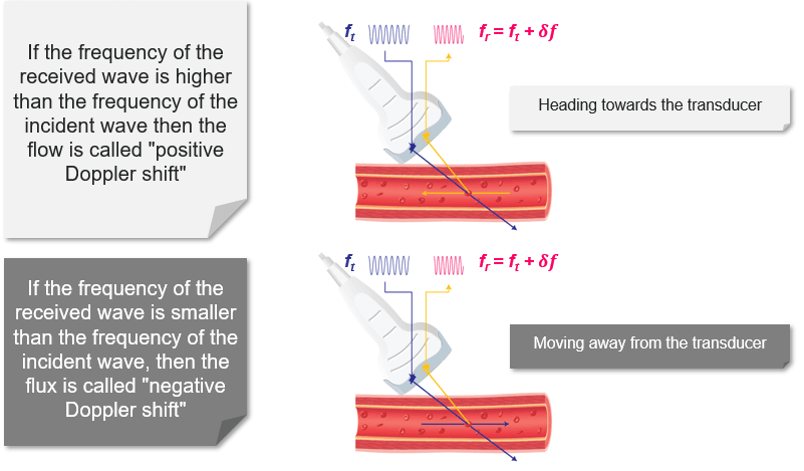

Direction and Speed of Flow

Blood flow moving towards the probe produces positive Doppler shifted signal. On the other hand, blood flow moving away from the probe produces negative Doppler-shifted signals. The image on the top illustrates the change in the received backscattered signals and the resulting Doppler shifts for blood moving towards the transducer. In this image, the relative direction of the blood flow with respect to the Doppler beam is towards the transducer, blood flow moving towards the transducer produces received signals (Fr) which have a higher frequency than the transmitted beam (Ft).

The Doppler-shifted signal (δf) can be calculated by subtracting Ft from Fr and produces a positive Doppler shifted signal. The Doppler-shifted signal (δf) can be calculated by subtracting Ft from Fr and produces a positive Doppler shifted signal. Whereas, the second image illustrates blood flow which is moving away from the probe. Blood flow moving away from the transducer produces received signals (Fr) of lower frequency than the transmitted beam (Ft). This time the Doppler-shifted frequencies (Fr − Ft) produce a negative Doppler shifted signal. It is important to note that when there is no flow or movement detected, the transmitted frequency (Ft) is equal to the received frequency (Fr). Therefore Fr = Ft and The Doppler-shifted signal (δf) = Fr − Ft = 0, resulting in no Doppler-shifted signals.